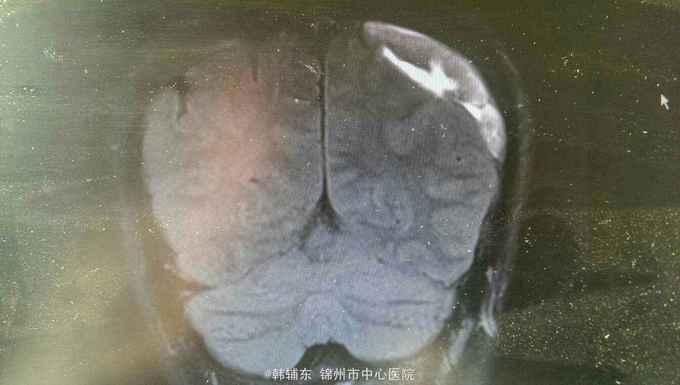

神志清楚,语言流利。神经系统无阳性体征,双侧瞳孔等大正圆直径3.0毫米,光反射灵敏。四肢肌力正常,生理反射存在,病理反射未引出。头部核磁共振显示如下。

诊断:亚急性硬膜下血肿。行血肿钻孔引流术。术后引出陈旧血,患者头痛缓解。

亚急性性硬膜下血肿绝大多数有轻微头外伤史,尤以老年人额前或枕部着力。亚急性颅内压增高症状常于伤后1~3个月后出现如头痛、视物模糊、一侧肢体无力等。精神智力症状表现为记忆力减退、智力迟钝、精神失常等。局灶性症状表现为轻偏瘫、失语等。亚急性或慢性硬膜下血肿MRI的T1和T2均表现为高信号。首选颅骨钻孔冲洗闭式引流术。对于血肿囊壁肥厚伴钙化须行骨瓣开颅清除血肿术。